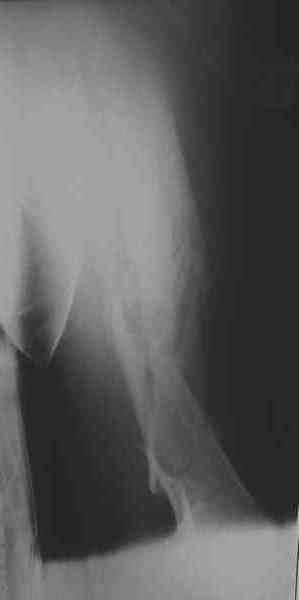

Уважаемые коллеги! Пришел на консультацию вот такой больной (первые 3-и рисунка). Травма автодорожная, апрель 2006г. Лечился консервативно, вытяжение и гипс. Через пять месяцев стал ходить. Укорочение бедра 6 см. 26 февраля 2007г. оступился, упал. Прооперирован в г.Баку - наложен стержневой аппарат. Ходит с костылями, наступая на левую ногу.

Мы попросили что нибудь из ранних снимков. Принес рентгенограммы перелома (рис. 4,5). Посмотрели, наснимали сами (рис. 6-10). Похоже, что нет сращения нигде. Хотелось - бы обсудить следующие вопросы: 1. дальнейшая тактика - реостеосинтез или подождать (ослабить аппарат, дать нагрузку и т.д.)? 2. если реостеосинтез - то чем и как? Юрий Алексеевич Булахтин